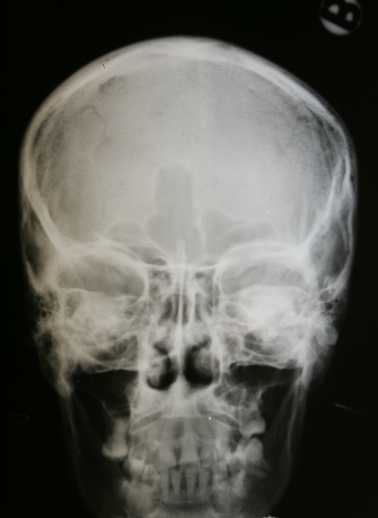

Постройка чрезвычайной хирургической больницы была закончена в 1944 году, когда сирены воздушных атак не переставали звучать и бомбардировка Будапешта была в полном разгаре. Больница имела полностью оборудованную операционную, средства рентгена, генераторы( независимые от сети города), В то время это был последний пик медицинских технологий. Однако, никакие технологии не могли справиться с тем, что ожидало больницу.